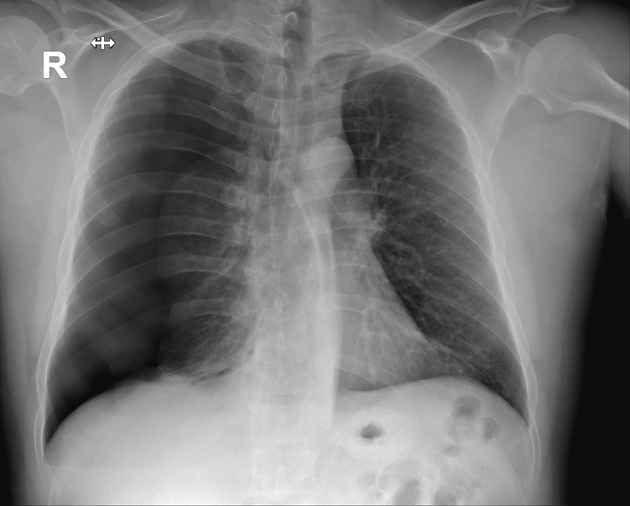

In the following image, identify the left and right lung and what separates the lobes (Provide at least one of the 2 correct answers)

The lung on the left is the RIGHT LUNG (3 lobes)

The lung on the right is the LEFT LUNG (2 lobes)

Lobes are separated by horizontal and oblique fissures.

Identify the condition in the following x-ray

Hint: To identify this condition, physicians will look for a shape cured white line as well as tissue that is pulled towards the center

Pneumothorax